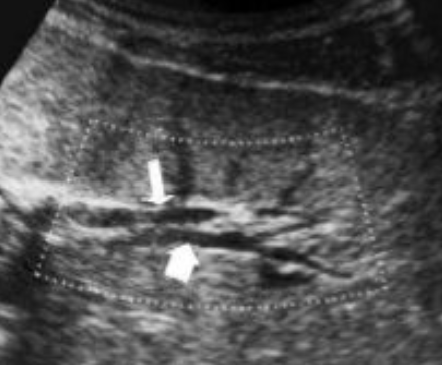

what is shown?

cervix sign in transverse indicating hypertrophic pyloric stenosis (HPS)

target sign in longitudinal plane indicating hypertrophic pyloric stenosis (HPS)